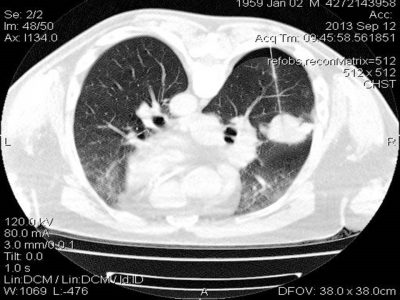

Παραδείγματα πότε μπορεί να βοηθήσει η εξέταση (ΕBUS) στη διάγνωση

- Χρησιμοποιείται για σταδιοποίηση του καρκίνου του πνεύμονα και έτσι αποφασίζεται εμπεριστατωμένα, αν ο ασθενής πρέπει να οδηγηθεί ή όχι στο χειρουργείο.

- Μπορεί να γίνει ταχεία βιοψία για άμεσο αποτέλεσμα.